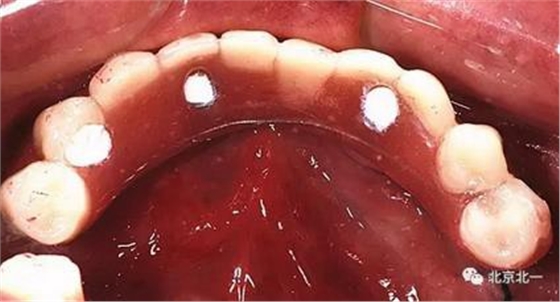

圖七:采用A04技術(shù),拔除下頜余留牙,修整骨平面。在頦孔前方傾斜植入兩枚植體,避開(kāi)頦孔。減少懸臂。前牙區(qū)植入兩枚直的植體。完成即刻修復(fù)。一日得牙,缺牙后多少年來(lái)都沒(méi)有吃過(guò)蘋果的滋味,到種植牙時(shí)代,想吃什么就吃什么, 我的健康我做主。

吃出健康,吃出風(fēng)采。 吃蘋果,平平安安。健健康康。八十歲種植不是夢(mèng)想。完美人生。